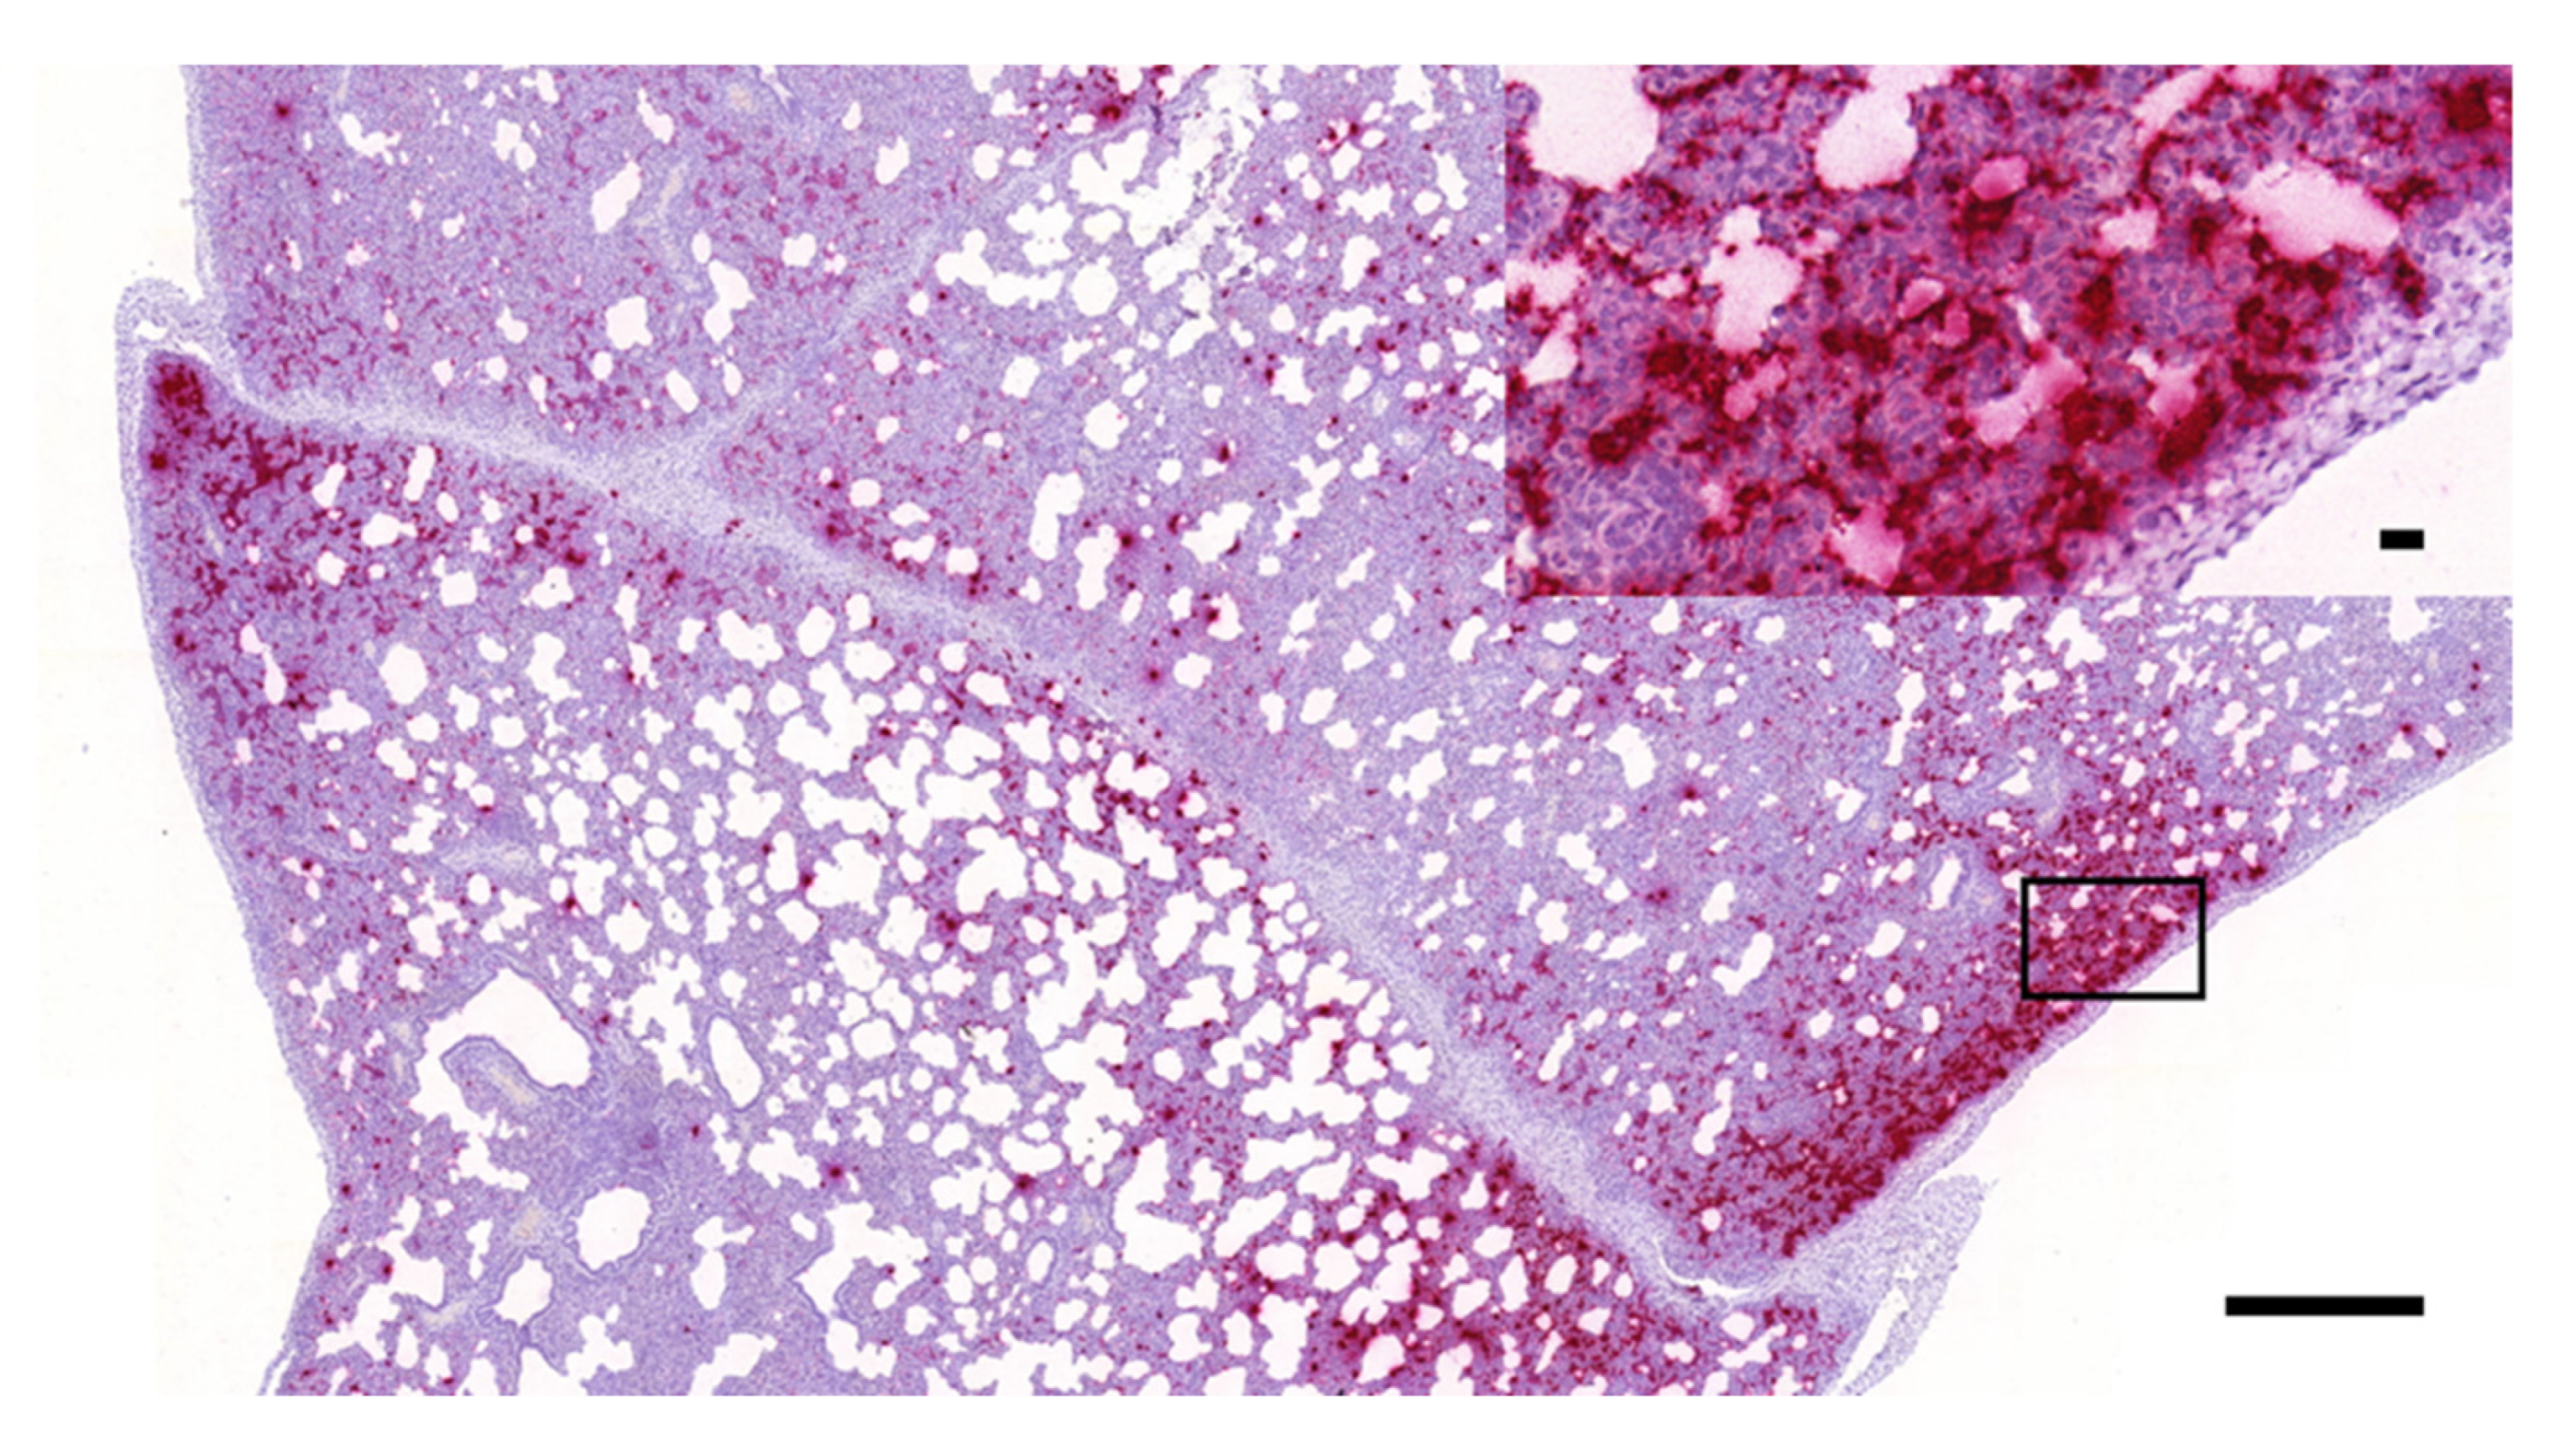

3.1. Histopathology and In Situ Hybridization